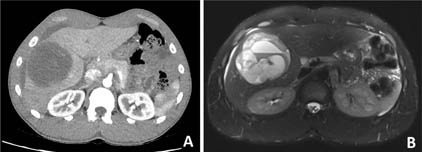

Imaging will demonstrate a heterogeneous liver mass with solid and cystic areas (8). There are usually no specific imaging features that can help suggest an undifferentiated embryonal sarcoma (2). On ultrasound, the tumor may appear more solid than cystic because of its high water content (7). On CT, UESL will be a hypodense solid and cystic mass (Figure 1A) (2). On MRI, the cysts within the mass may show multiple fluid-fluid levels (Figure 1B) (9). Due to their cystic character radiologically, UESLs have been known to be mistaken for benign cystic entities such as biliary cystadenomas, hydatid cyst disease, or venolymphatic malformations (2, 8, 9). In fact, the radiological appearance of USEL can be quite misleading to a point where delays in diagnosis or even the initiation of the wrong treatment have occurred (4, 10).

Figure 1. Radiology of undifferentiated embryonal sarcoma of the liver (UESL). A. An arterial phase contrast-enhanced computed tomography from a young adult male with UESL. It demonstrates a large hypodense mass in the right lobe of the liver. B. Magnetic resonance image showing a large mass in right lobe of the liver with heterogenous and cystic features along with fluid-fluid levels.